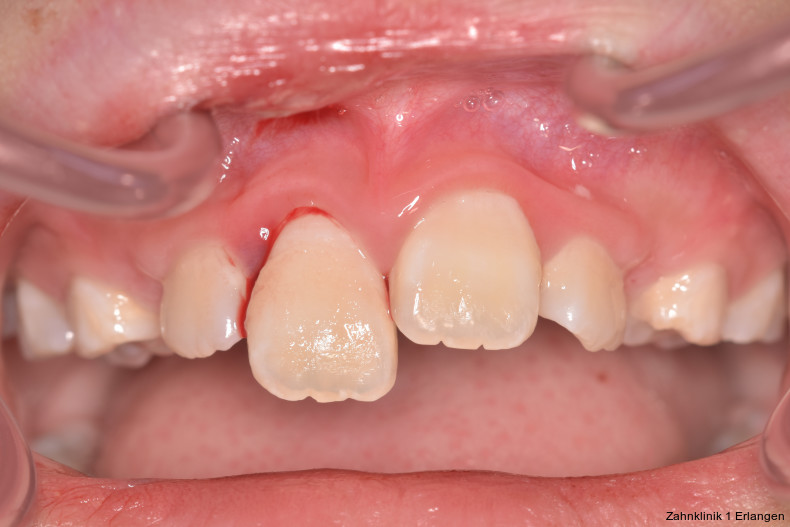

Zu den Zahnfrakturen mit Pulpabeteiligung gehören die in das Dentin reichende unkomplizierte Kronenfraktur sowie die komplizierte Kronenfraktur mit Pulpaexposition. Rein schmelzbegrenzte Frakturen sind hinsichtlich des Pulpastatus als unkritisch einzuschätzen.1 Dislokationsverletzungen betreffen die Pulpa insofern, als das Gefäß-Nerv-Bündel je nach Ausprägung der Positionsveränderung gestaucht, gedehnt oder abgerissen sein kann. Bei Zähnen mit abgeschlossenem Wurzelwachstum geht man davon aus, dass spätestens ab einer Dislokation von 2 mm die Pulpa abgerissen wurde, was die zeitnahe Einleitung der Wurzelkanalbehandlung notwendig macht.2, 3 Bei geringer ausgeprägter Dislokation kommt den Nachkontrollen eine wesentliche Rolle zu, bei denen jeweils dem Pulpastatus besonderes Augenmerk zukommen sollte, um eine Pulpanekrose frühzeitig zu detektieren.

Zu den wesentlichen diagnostischen Verfahren, die zur Erfassung des Pulpastatus herangezogen werden, gehören neben der Inspektion und der röntgenologischen Bildgebung die Sensibilitätsprüfung sowie der Perkussionstest. Der Inspektion kommt insbesondere bei der Erstbehandlung eine wesentliche Rolle zu. Hierbei wird abgeklärt, ob es sich bei Zahnfrakturen um eine schmelzbegrenzte Verletzung handelt, ob das Dentin mitbetroffen und ob zusätzlich die Pulpa exponiert ist. Bei Dislokationsverletzungen wird das Ausmaß der Positionsveränderung erfasst und ob zusätzliche Gewebe wie Knochenstrukturen oder umliegende Weichgewebe betroffen sind. Auch können Farbveränderungen des Zahnes erfasst werden. Die Röntgendiagnostik zum Zeitpunkt des Unfalles gibt Aufschluss über die Größe des Pulpenkavums und das Lumen des Wurzelkanals, den Stand des Wurzelwachstums und die periapikalen Verhältnisse. Des Weiteren finden sich möglicherweise Hinweise auf eine Wurzelfraktur.

Unkomplizierte Kronenfrakturen mit Verlauf im Dentin sind als Wundfläche einzuschätzen, bei der es bei anhaltender Exposition zum Mundhöhlenmilieu zur Infektion der Pulpa über freiliegende Dentintubuli kommen kann. Somit ist ein wesentlicher Grundsatz der Erstversorgung, die Dentinwunde abzudecken,3, 8 vor allem bei jungen Patienten mit großlumigen Dentintubuli. Die Abdeckung kann im Zuge der Notfallbehandlung mit Glasionomerzement erfolgen oder mittels fließfähigem Komposit unter Verwendung eines Dentinadhäsivs. Hilfreich im Hinblick auf die spätere Wiederentfernung ist dabei die Verwendung eines falschfarbenen oder opaken Materials, um die provisorische Abdeckung bei der definitiven Versorgung gezielt wieder entfernen zu können. Bei pulpanahen Verletzungen empfiehlt sich die Abdeckung mit einem biokompatiblen Material wie hydraulischem Kalziumsilikatzement oder Kalziumhydroxid im Sinne einer indirekten Überkappung.3 Betroffene Zähne können durch Wiederbefestigung des Zahnfragmentes9 oder mit Komposit restauriert werden, dies kann jedoch auch erst bei der Weiterbehandlung erfolgen.

Bei Pulpaexposition ist die oberste Prämisse der Erhalt der Vitalität des Zahnes. Vor allem bei jungen Patienten und bei nicht abgeschlossenem Wurzelwachstum, aber auch bei erwachsenen Patienten ist die Vitalerhaltung die Methode der Wahl. Dabei spielen die Dauer und die Größe der Exposition keine wesentliche Rolle.10 Die oberste Gewebeschicht sollte zunächst im Sinne einer Mikropulpotomie angefrischt werden, was mit einem Diamantschleifer unter Wasserkühlung durchgeführt werden kann. Nach Blutstillung, zu der Natriumhypochlorit tropfenweise appliziert werden kann, wird das Sistieren der Blutung kontrolliert. Ist dies verifiziert, wird ein biokompatibles Material in direktem Kontakt mit dem Gewebe aufgebracht und der Zahn anschließend adhäsiv verschlossen.10 Dauert die Blutung an, beispielsweise weil der Unfall bereits mehr als 24 Stunden zurückliegt, kann tiefer pulpotomiert werden. Da eine traumatisch geschädigte Pulpa in der Regel vor dem Unfall gesund war, ist die Heilungskapazität meist sehr gut.11 Auch bei bestehender Exposition zur Mundhöhle hin über einen Zeitraum von Tagen kann die Pulpotomie noch hohe Erfolgsraten erzielen.